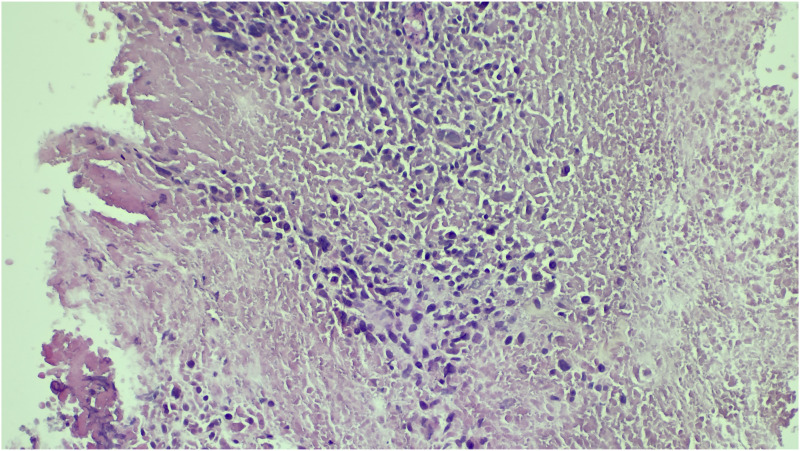

Cardiac metastases are the most frequent cardiac tumors. They can cause dysrhythmia, myocardial dysfunction, pericardial effusion, and heart failure. In decreasing order, the major primary malignancies associated with cardiac metastases are pleural mesothelioma, lung adenocarcinoma, undifferentiated carcinomas, lung squamous cell carcinoma, and breast carcinoma. Cardiac metastasis of sarcomas is uncommon, and only a limited number of cases have been found in literature. We report the case of an incidentally discovered cardiac metastasis when assessing the extension of a thigh mass in a 45-year-old man.

Abstract Image